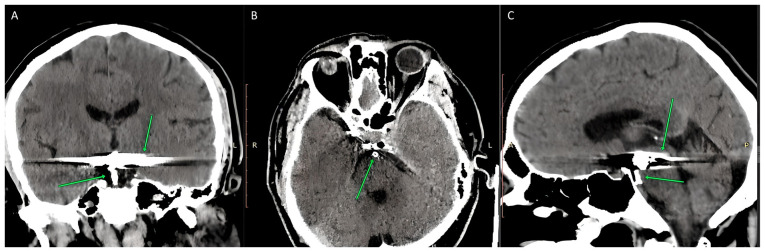

The present study described the case of a 50-year-old male patient. The patient had type 2 diabetes since the age of 38 years (in 2013) with an initial elevated glycated hemoglobin A1c of 7.2%, with a significant cardiovascular (CV) history consisting of an aneurysm of the anterior communicating artery that had been operated on in 1998 and a ruptured basilar artery tip aneurysm embolized with a stent in 2013; the case was also associated with bronchiectasis (since 2020), non-alcoholic fatty liver disease (since 2018), diabetic neuropathy (since 2023) and obesity with a body mass index of 31.72 kg/m2 (since 2010). Over the years the patient exhibited good metabolic control, initially treated with Metformin and managed through a change of diet. However, due to intolerance to Metformin, the patient stopped receiving treatments and only managed his diet. Since diabetes is by definition a condition that implies a high CV risk by itself, the primary focus with this patient was to provide additional CV protection, particularly secondary protection against any other potential future, and possibly fatal, CV events. After a brief introduction regarding the available therapeutic options, the case is presented along with the medical history, concomitant medications and evolution after 1 year. In the discussion section, similar documented cases in the literature were compared with the present case, and the potential effects of the therapeutic intervention in the present study were compared.